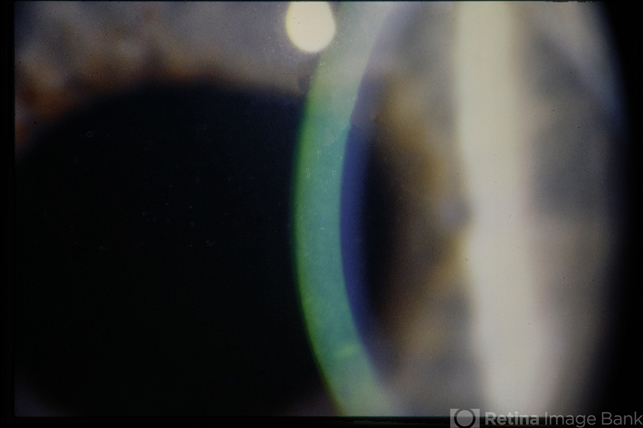

- Anterior Basement Membrane Dystrophy

- Slit lamp photo of dots.